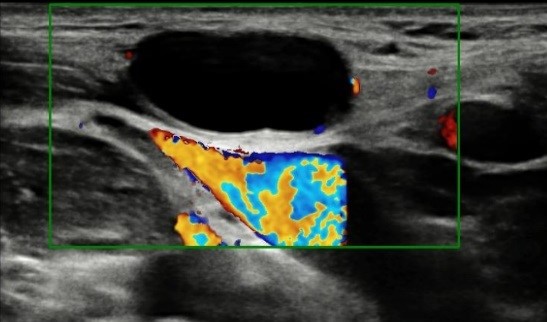

Un mes después volvieron a consulta refiriendo hiporexia y aparición de más adenopatías, una de ellas en la región anterolateral baja del cuello, de consistencia gomosa y dolorosa al tacto. Se repitió la analítica con serologías (sin alteraciones) y se solicitó Mantoux (0 mm de induración). También se realizó una ecografía en la que se observaron múltiples adenopatías (imágenes ovaladas, menores de 1 cm, con hilio central y bordes bien definidos), y en el tercio distal del esternocleidomastoideo una imagen anecogénica ovalada de bordes bien definidos sin flujo con Doppler (Fig. 1).

| Figura 1. Ecografía en la que se observan múltiples adenopatías |